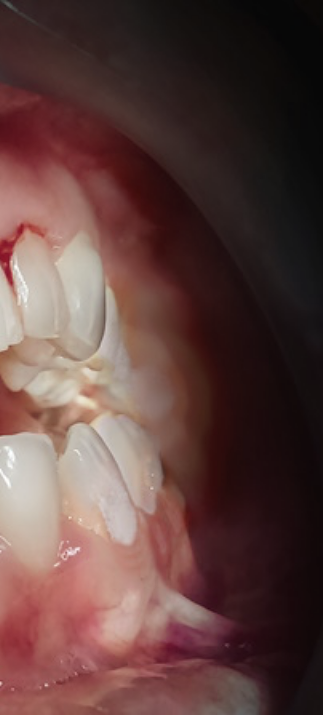

첫번째 치은염 증상은 바로

잇몸의 붓기와 출혈이였어요.

평소 치실로 꼼꼼하게 양치를

해주시는 분들의 경우 잇몸에서

피가 나는 것은 흔한 현상이지만

이러한 증세가 지속적으로 자주

발생한다면 이는 치은염으로 인한

현상은 아닌지 의심해보셔야 했어요.

두번째 증상은 잇몸이 붉게 변하며

붓기가 생기는것인데요.

건강한 잇몸은 연분홍색을 띄며,

잇몸에 염증이 발생하면 빨갛게

부워오르게 된다고 했어요.

이러한 경우 잇몸이 예민해져 있어

살짝만 칫솔로 건드려도 출혈이 쉽게

발생하며 통증 또한 느껴질 수 있는

부정적인 상태에 해당됐어요.